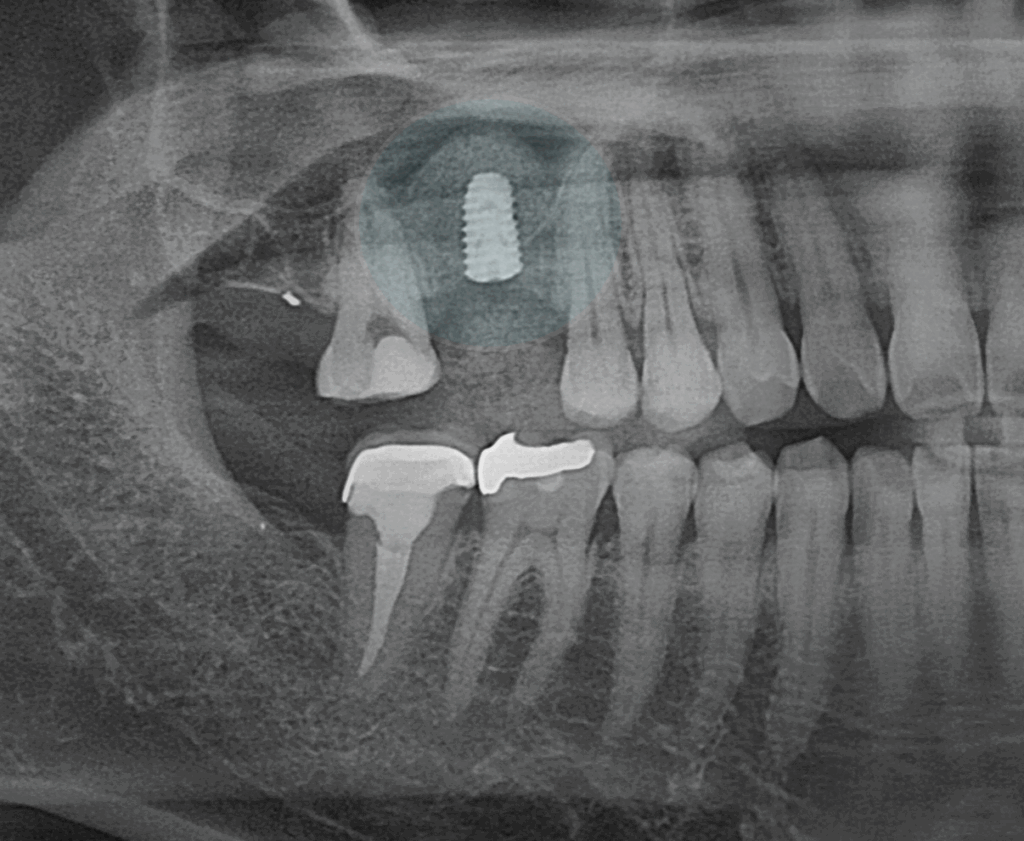

먼저 민락 치과 에서

사진에 표시한 곳을 보겠습니다.

민락 치과 에서 설명해 드린

충치가 진행된 어금니 외에도

눈에 띄는 부위가 있습니다.

그 앞쪽으로 결손된 곳으로,

텅 비어 있는 모습이 확인됩니다.

인접한 잇몸 조직에 비해서

다소 움푹 패인 모습을 보여주는데

이것은 치아가 결손된 부위가

그대로 방치된 케이스들에서

공통적으로 나타나는 문제입니다.

사진을 보면 상악동 거상술이

잘 마무리된 것이 확인됩니다.

충분한 공간이 확보되어

상악동에는 큰 영향이 없이

픽스처가 자리 잡고 있습니다.